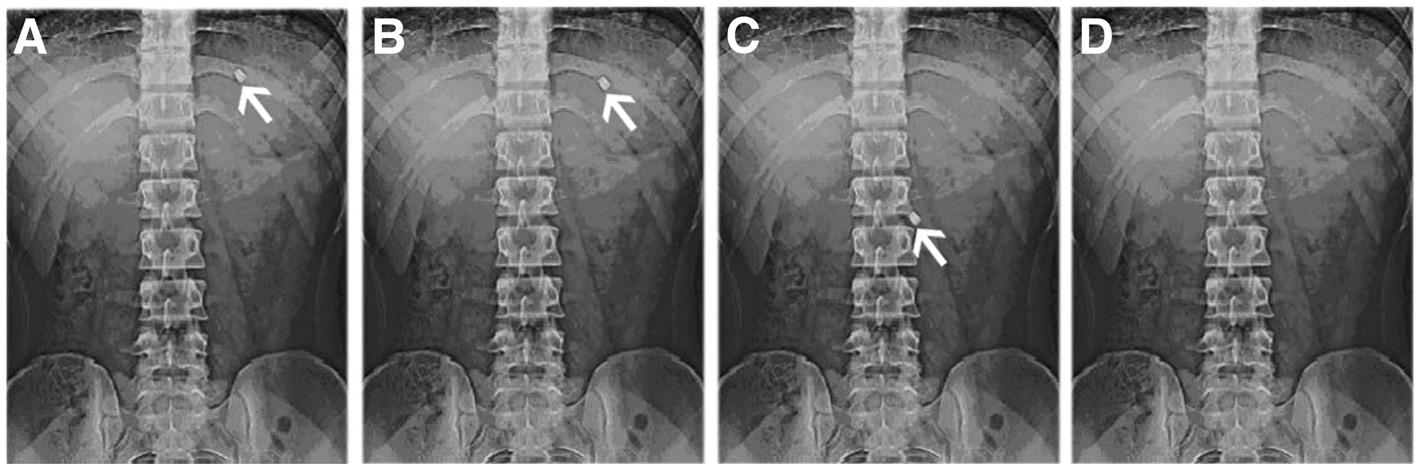

The buoyancy of developed BGRFT under fasted conditions was observed on the gastric fluid at 2nd hr as shown in fig. 10 (aandb) and in the small intestine after 4 h as shown in fig. 10 (c) and was disappeared at 6th h as shown in fig. 10 (d). As a result of this activity, dosage form administered to fasted subjects could be emptied as rapidly as within an hour or two, depending on the presence of the strong motor induced contractile activity [19].

Fig. 10: X-ray photographs of gastric floating tablets of bilayer gastric retentive floating tablets containing ranitidine HCl and clarithromycin under fasted state after (a) 0.5 h (b) 2 h (c) 4 h and (d) 6 h